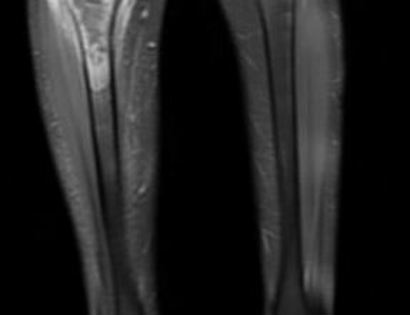

Pre-Op MRI of Tumor

This is an MRI of the patient with a tumor located in their right tibia (upper left side of the image).